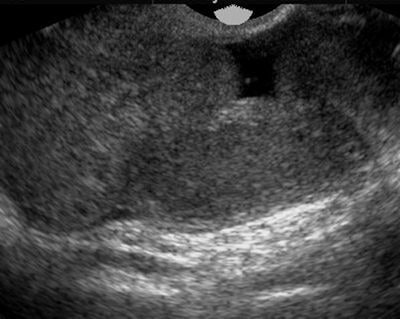

| Pyosalpinx: Patient presented with lower abdominal pain and increased inflammatory markers. Transvaginal ultrasound demonstrated dilated serpentine structures with internal echogenic debris representing infective pus within the fallopian tubes. |